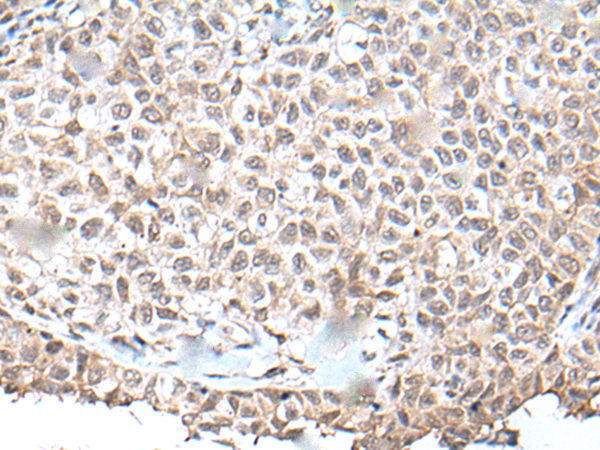

IHC positive control:

Human ovarian cancer and human tonsil

IHC Recommend dilution:

50-300